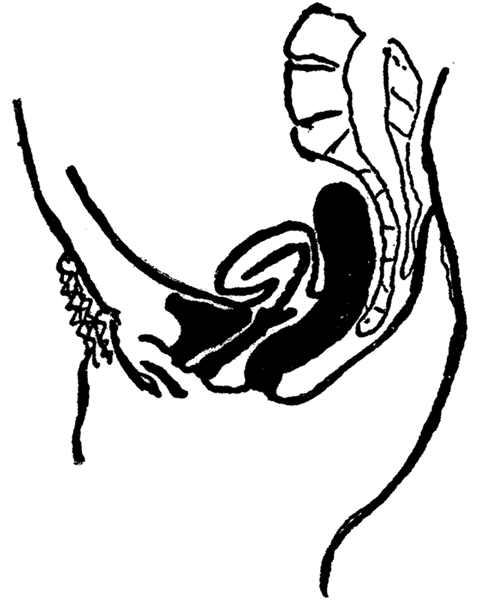

The uterus is situated in the center of the pelvis, between the bladder and the rectum. It is supported by certain ligaments, the chief of which are the broad ligaments; but, on account of general weakness, too hard physical labor, or lifting heavy weights, the ligaments may stretch, and the uterus may sink down low in the vagina, and we then have the condition known as prolapse of the womb. Or, the womb may turn forward, when we have a condition of anteversion. If the womb is bent (or flexed) forward on itself the condition is called anteflexion. If the womb is turned backwards, the condition is called retroversion; if it is bent or flexed backward upon itself the condition is called retroflexion. An extreme degree of anteversion or anteflexion, or retroversion or retroflexion, may interfere with impregnation, as the spermatozoa may find it difficult or impossible to reach the opening of the womb—the external os.

Retroversion of the Uterus.

Retroflexion of the Uterus.